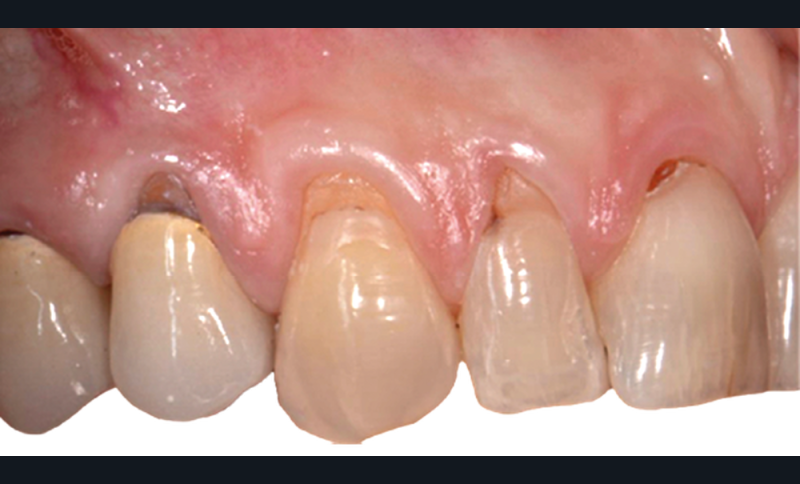

Le lambeau coronairement avancé multiple (MCAF), proposé par Zucchelli et de Sanctis (2 000), est devenu la procédure de couverture radiculaire la plus largement utilisée pour les défauts de récession multiples. Il présente une évolution technique et esthétique du lambeau d’avancée coronaire avec incision de décharge qui n’est désormais plus recommandé. Ce lambeau est défini par son tracé d’incision autour de la récession principale et par son épaisseur en partielle-totale-partielle (« Split-Full-Split »).

Le tracé d’incision papillaire, très précis, permet d’éviter les décharges. Il consiste à réaliser des incisions para-marginales obliques qui vont toutes être orientées en direction de la récession la plus sévère, ce qui permet d’obtenir un lambeau déplacé avec une légère rotation des papilles.